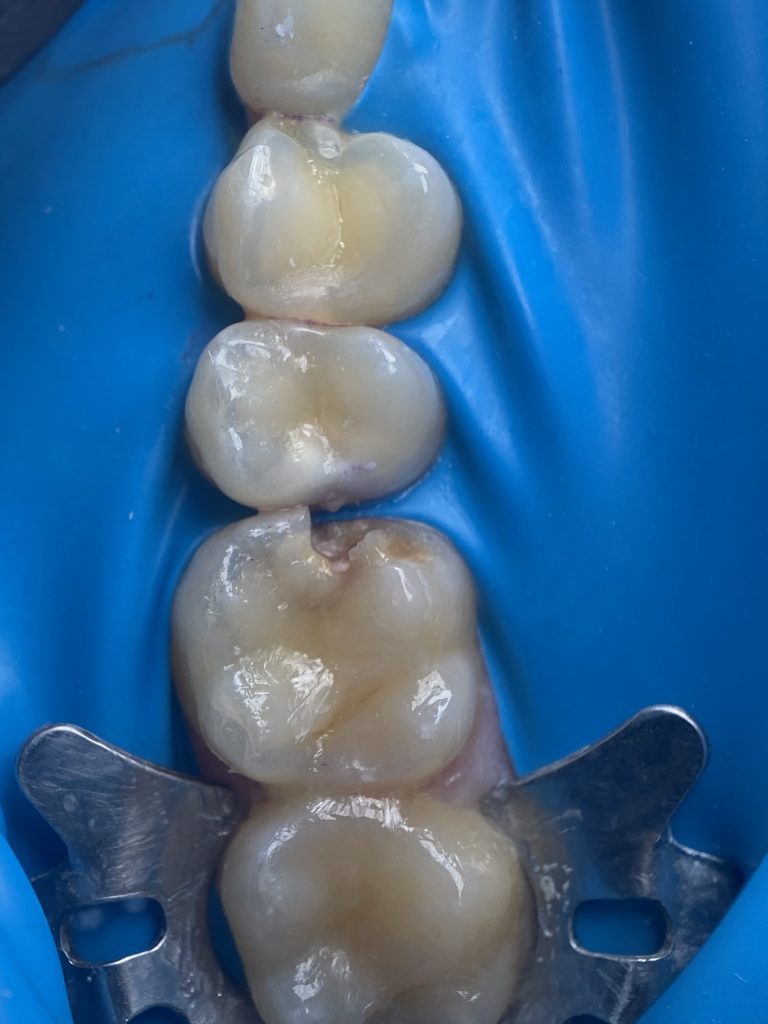

-Finishing

*The cusp was completed with bulk-fill flowable composite to correctly position the matrix band and prevent the ring from deforming the band and disrupting the emergence profile.